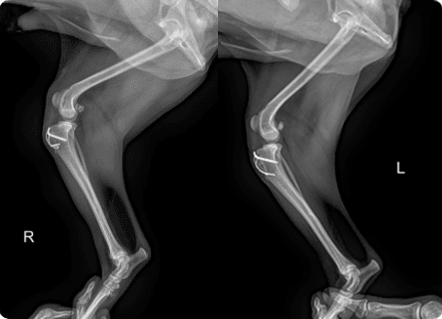

골절, 골종양 등

일산시티동물의료센터의 투시검사는 정형외과 수술에 이용할 수 있으며

일산시티동물의료센터 방사선(X-ray) 검사는 탁월한 영상품질로 세밀하고 선명한 영상을 얻을 수 있습니다.